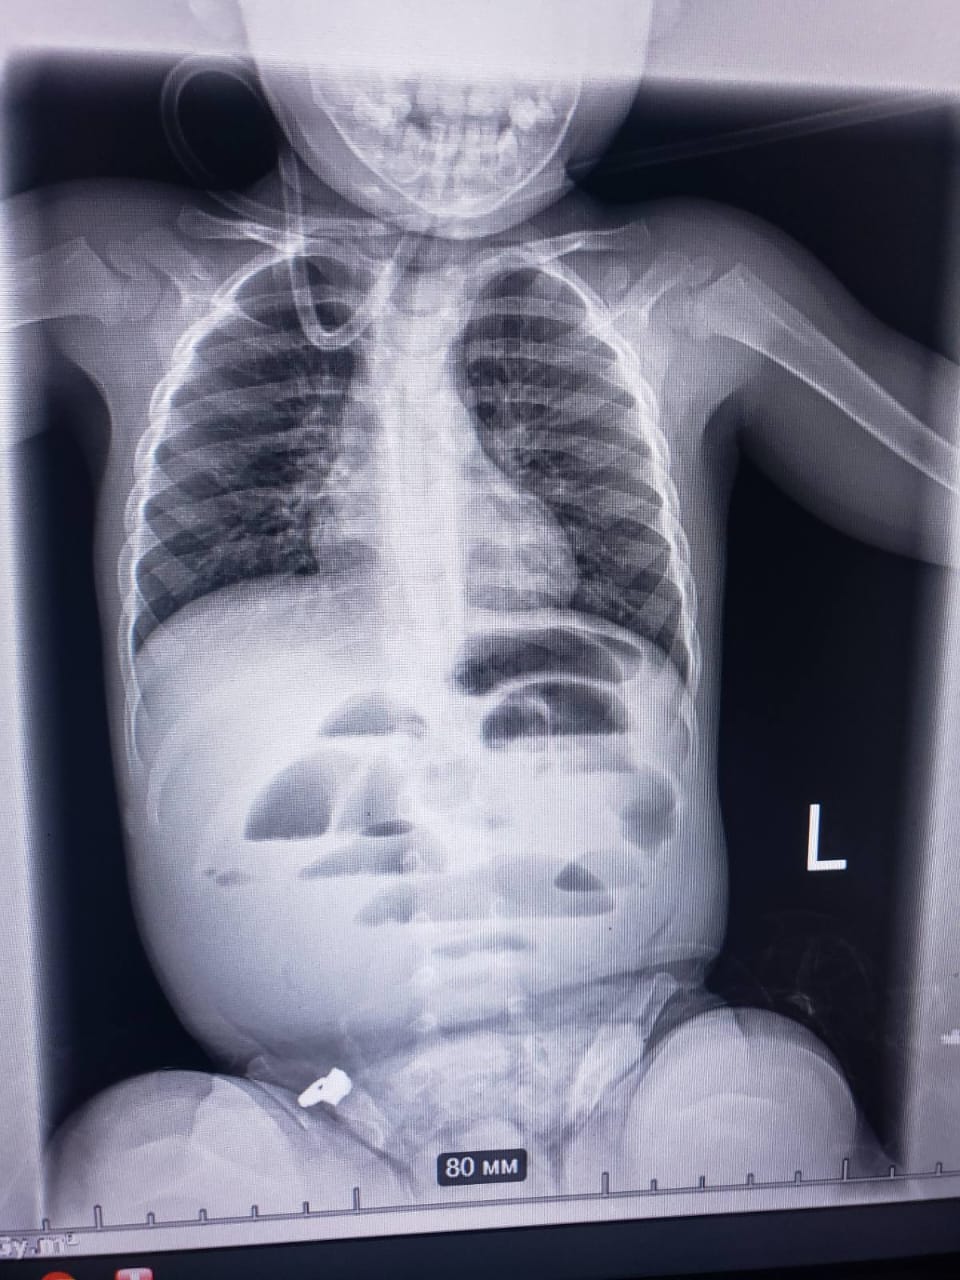

В одну из больниц Днепра обратились родители ребенка, которому всего 1 год и 8 месяцев с жалобой на кишечную непроходимость, передает "Відомо" с ссылкой на Региональный медицинский центр семейного здоровья.

Медицинские работники на рентгенограмме органов брюшной полости ребенка выявили признаки кишечной непроходимости и в составе мультидисциплинарной команды врачей приняли решение провести срочную операцию.

Когда ребенка доставили в операционную — провели оперативное вмешательство и обнаружили постороннее тело, полностью перекрывшее просвет кишечника.

Предметом стал гидрогелевой шарик, который в организме ребенка увеличился в размере вплоть до 3 см.

Гидрогелевый шарик изъяли, ребенку наложили швы и перевели в отделение интенсивной терапии. Сейчас жизни малыша ничего не угрожает.